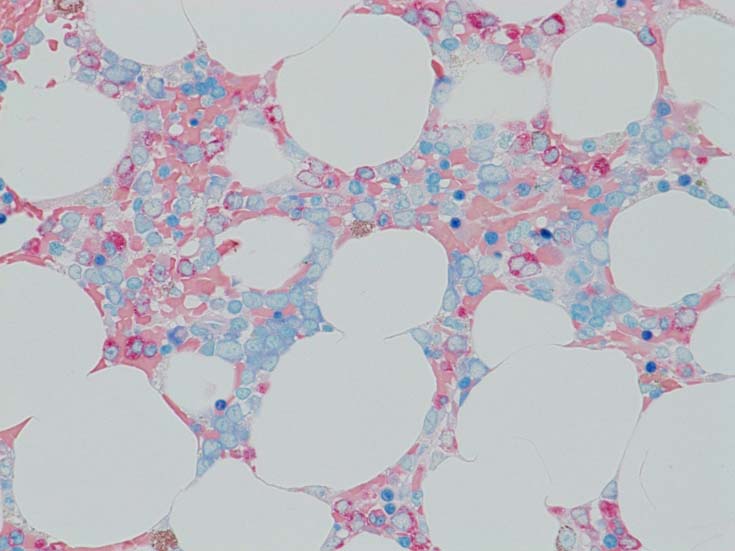

MDS症例のHbF発現.

サムネイル画像をクリックすると大きな画像が見られます.

MDSでの赤芽球HbF発現は, 陽性細胞はそれほど多くない印象ですが, この低形成性MDS症例では, 多くの陽性細胞がaggregatesを形成していました.